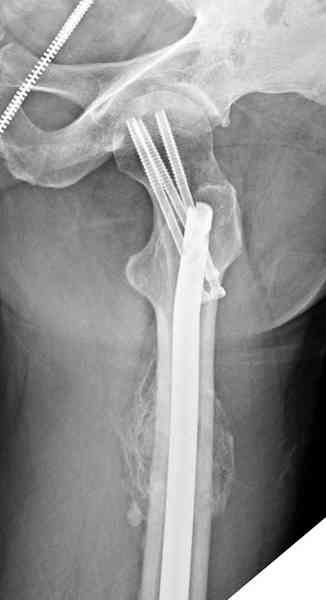

В первый же день произведено антеградное штифтованием DePuy Trochanteric Nail.

На второй день (7) обнаружен пропущенный перелом,

сделаны Компьютерная Томограмма

и проведены шурурпы через и спереди штифта без удаления.

Послеоперационные снимки